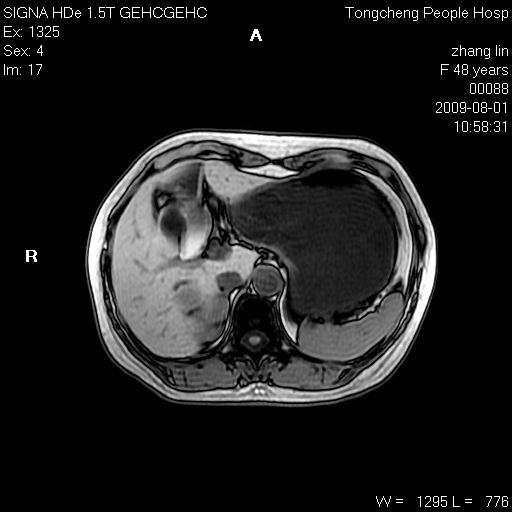

女,48岁。健康体检,彩超发现右肾占位性病变。平素健康。

临床诊断:右肾占位性病变,性质待定(囊肿?肿瘤?)。

上中腹部mr平扫+增强扫描,图像如下:

右肾上极见一类圆形病灶,t1wi呈等信号t2wi呈等高混杂信号,三期增强无强化,边界清---考虑囊肿出血。

同反相位均表现为等信号,病变无强化,考虑含蛋白的囊肿可能,弥散加权相或许有些帮助,

慢性胆囊炎